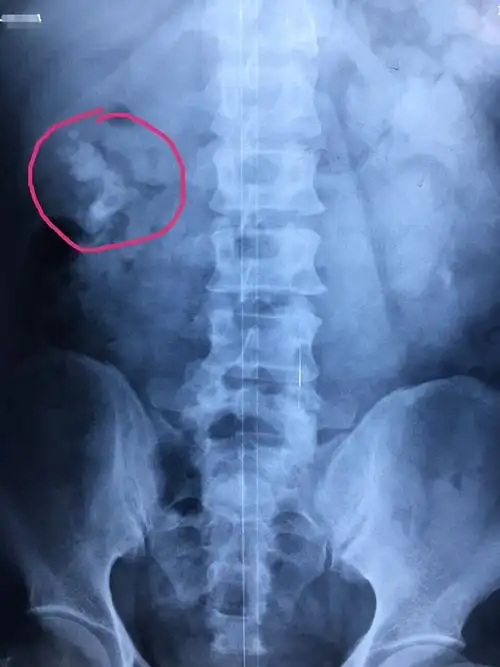

肾脏巨大铸型结石病例治疗

ct影像显示巨大肾结石(红圈内)